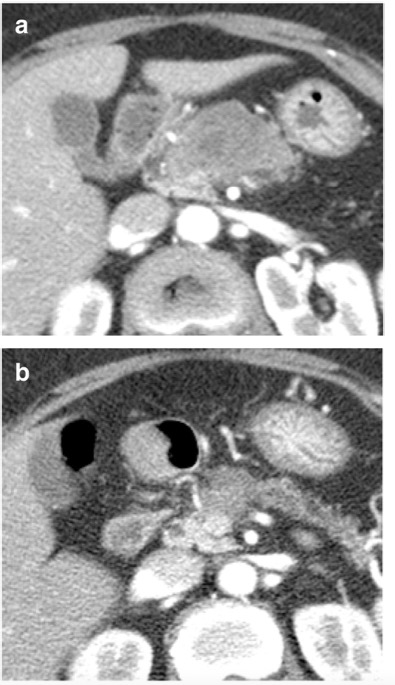

70歲女性,因胰腺癌接受新輔助治療。(a)在診斷時和(b)新輔助治療后的增強(qiáng)CT圖像。所有六位讀者對再分期CT的腫瘤可切除性評估為 "邊-可切除"。五位讀者評估腫瘤反應(yīng)等級為1(反應(yīng)良好)。由于腫瘤周圍的纖維化和粘連,進(jìn)行了門靜脈/腸系膜上靜脈切除和端對端吻合術(shù),但病理檢查沒有靜脈侵犯的證據(jù)。切緣為陰性,YpT2N0分期。